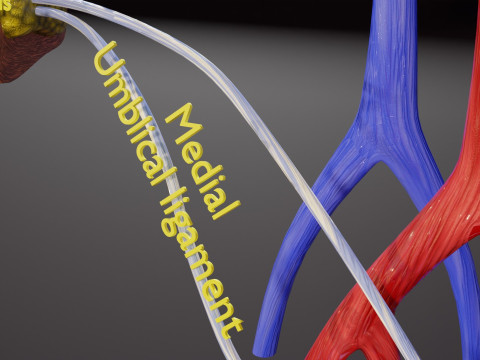

The model meshes include adult circulation versus circulation in Tetralogy of Fallot (TAF), arrow labels and text labels. The blood flow in a patient with Tetralogy of Fallot is outlined in this model. To contrast it to normal blood circulation a separate model of normal circulation is included. The Tetralogy of Fallot (OVER RIDING OF AORTA, PUL STENOSIS, VENTRICULAR SEPTAL DEFECT, RIGHT VENTRICULAR HYPERTROPHY), fossa, ligament teres , venosus, and arteriosus are duly depicted with proper labelling and blood flow directional arrows. Excellent model for teaching, demonstration and knowlegde of human body. The models include both procedural and image textures blend files separately. The texture file include diffuse, roughness and normal png and jpeg based on non overlapping UV maps.